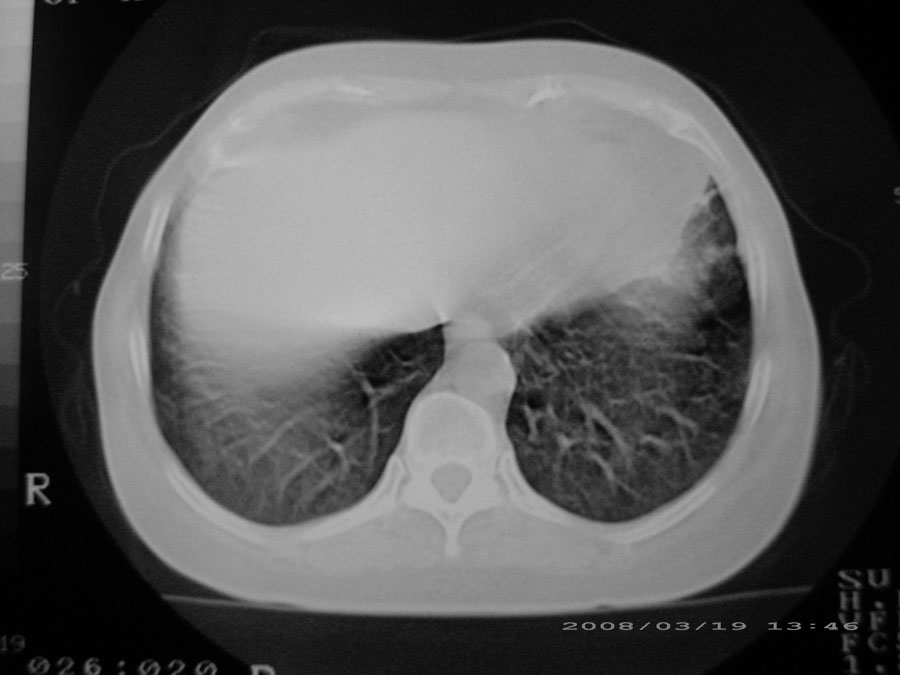

密漫性沿纹理走行小结节影;有间质纤维化;可考虑尘肺;以图而论

两肺间质性病变!考虑间质纤维化?间质性肺炎!

综合大家意见,结核、结节病、肺泡细胞癌均有可能,间质性肺炎暂不考虑,病灶纠集不明显,纵隔未见钙化淋巴结,尘肺可能性不大,但还是要密切结合临床诊断。

今天重新仔细看了看,矽肺确实不能除外,病灶主要表现为间质结节及纤维化。好好问问病史吧。